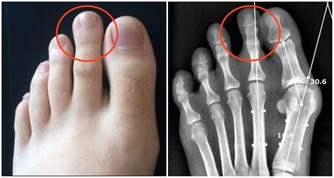

冬季做好防寒工作,防止寒邪和風邪入侵身體。尤其是頭部胸腹部以及腳部的保暖。當天氣寒冷時會讓頭部的血管收縮,從而引起頭痛頭暈,增加了患上腦血管疾病的機率。若寒氣入侵胸腹部時會損害到陽氣,對胃腸道功能以及心臟帶來損傷。保持平和的心態,多和朋友或者家人溝通,適當的延長光照的時間,多參加戶外活動或者聽聽輕音樂來調養體質。